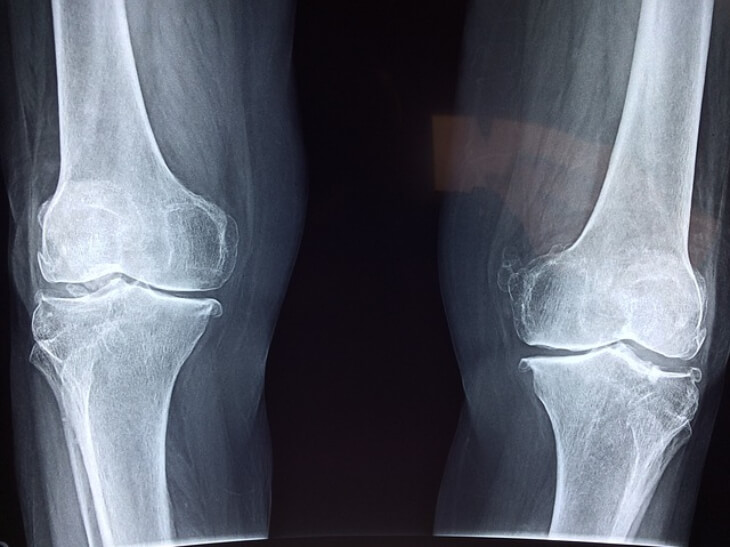

③ 뼈와 연골 건강

미네랄을 제외한 뼈를 구성하는 단백질 중에서는 90% 이상이 콜라겐으로 이루어져 있습니다. 연골의 ECM도 콜라겐이 차지하는 비중이 50~60% 정도로 높은데요.

나이가 들면 뼈의 골량도 점차 감소하게 되어 골다공증이나 골절의 위험이 높아지게 됩니다. 콜라겐 섭취는 골밀도를 증가시키고 뼈 질환을 예방하는데 도움이 됩니다.

또 체내 콜라겐이 증가하면 연골 조직의 염증을 감소시켜 관절염이나 관절 장애 등의 전반적인 통증을 완화하는데도 도움이 됩니다.